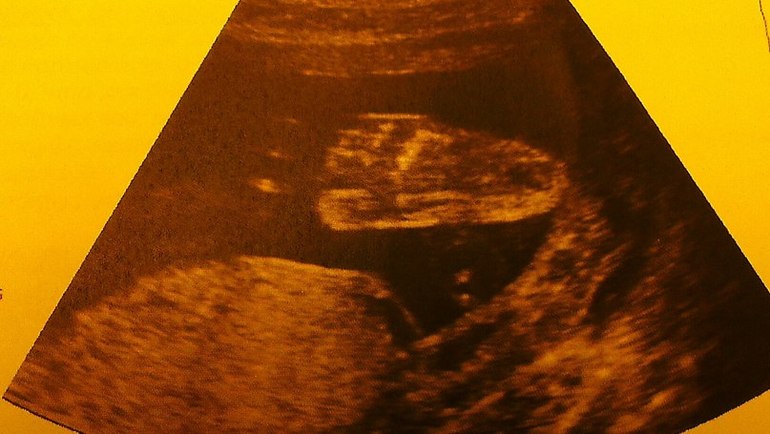

Пол малышаВчера были на узи. По совету двух подруг поехали в ЦИР (мне там очень понравилось!). Они смотрят сразу во всех форматах 2D-3D-4D - так здорово все видно! На прошлом узи, пролежав 20 минут, малышик так и не захотел показать пипильку -закрыл ее пятками и сдаваться не хотел. В этот раз наконец-то удалось подсмотреть! У нас маленькая Бусинка!! Такая красивищная, прям мимими

Папа был настроен на парнишку, но главное, что малышик по всем показателям хороший, все в норме, а еще мы длинююююющие ( мы с папой тоже высокие) - узист обещала модель

И такая скромница - дав все рассмотреть врачу, закрыла попу и писюльку ладошкой